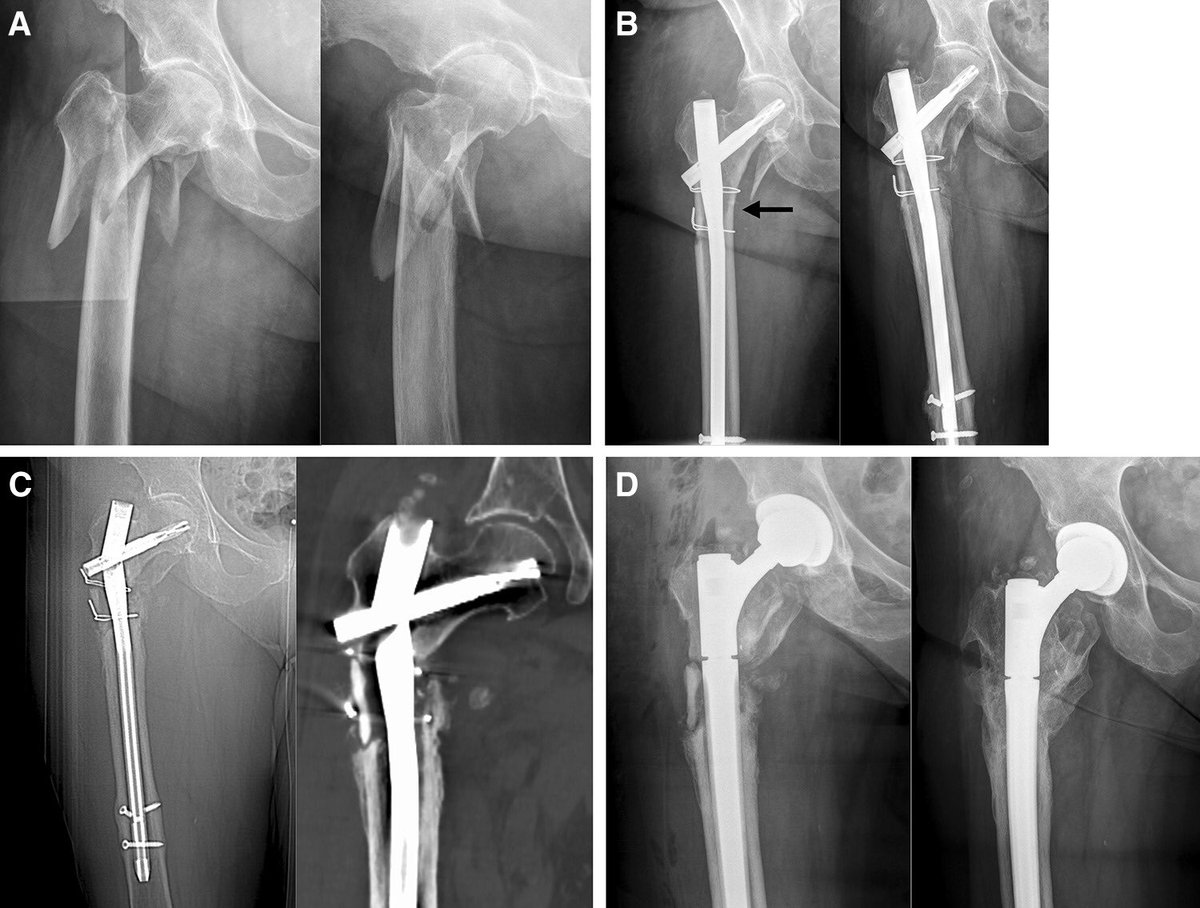

⛔️دعونا نوقف الكسور العظام الناتجة عن هشاشة العظام ⛔️

⬅️هشاشة العظام تؤدي الى حدوث الكسور 💥في عظام الحوض او الورك او الظهر او رسغ القدمين من مجرد وقوع بسيط لدى كبار السن

✅امراءة من كل ٣ نساء ورجل من كل ٤ رجال يعانون من كسور العظام فوق سن الخمسين

✅كسور العظام تكلف وتعطل الاقتصاد وتسبب العجز الجزئي أوالكلي وتزيد من نسبة الوفاة لدى كبار السن